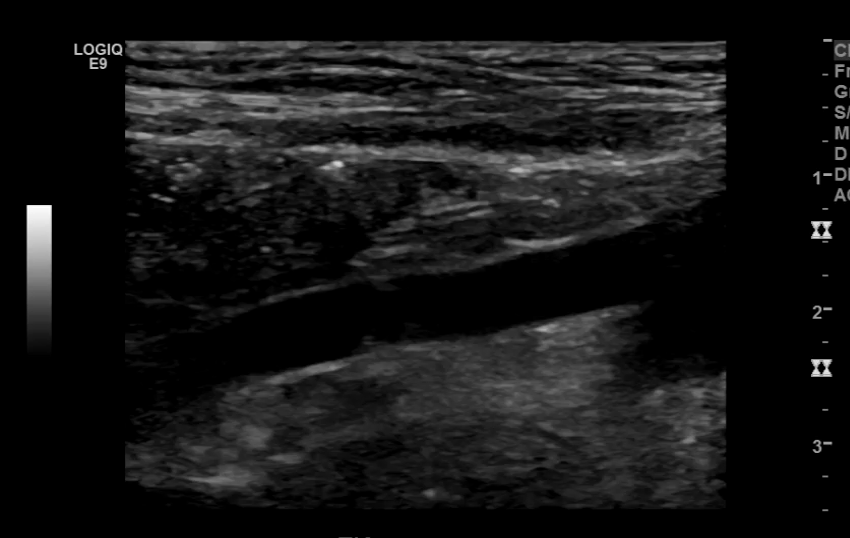

The iliac arteries bifurcate into external and internal iliac arteries (EIA and IIA). The EIA continues caudally turning into the common femoral artery (CFA) which further bifurcates into superficial femoral (SFA) and deep femoral artery (aka profunda femoris). The SFA then converts into the popliteal artery which bifurcates into the tibioperoneal trunk and anterior tibial artery (ATA). The tibioperoneal trunk bifurcates into posterior tibial artery (PTA) and the peroneal artery. The anterior tibial artery descends further to become the dorsalis pedis artery (DPA).

CFA and its branches